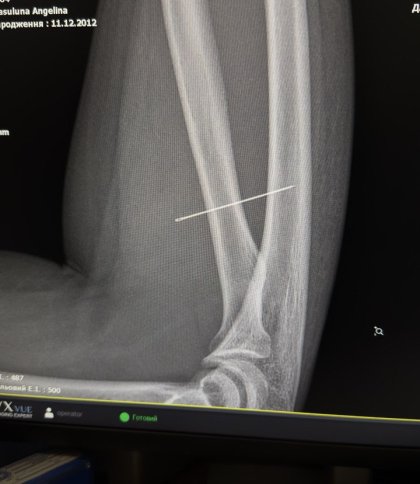

Під час огляду лікарі запідозрили сторонній предмет і направили дитину на УЗД м’яких тканин, де й виявили голку. Згодом рентген підтвердив, що вона зайшла під кутом 45 градусів і застрягла глибоко в товщі м’яза, продовжуючи мігрувати всередині тіла.

Під час операції лікарям було критично важливо витягнути голку точно за траєкторією її входження, аби вона не зламалася. За допомогою рентген-навігації ЕОП хірурги точно визначили місце стороннього тіла, виконали невеликий розріз і безпечно його видалили.